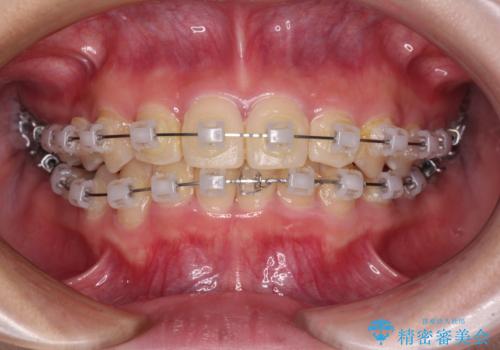

- クリアブラケット

- 1年2ヶ月

犬歯は歯根が太くて長いため、クロスバイトを改善するのは大変であることが多いですが、比較的スムーズに改善することができました。